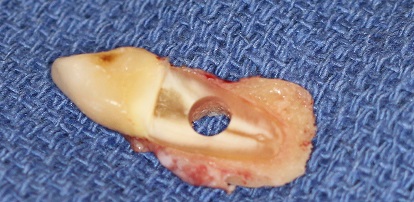

On arrache une dent au patient ainsi qu’un morceau d’os de la mâchoire, et on perce un trou dedans:

On glisse un petit cylindre en plastique dans le trou. Il servira de lentille artificielle.